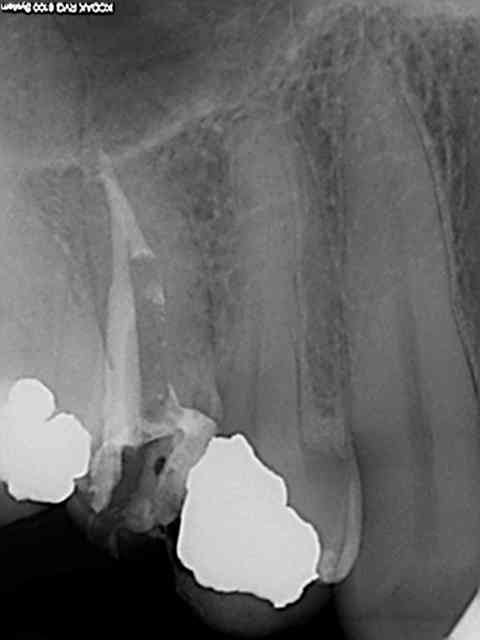

les pivotmatics sont calibrés pour 10 mm (rouge) ou 11 mm (bleu)de logement de tenon. C'est un peu emmerdant lors du mordu que le pivomatic touche l'antagoniste. Leur diamètre en outre sont supérieurs au largo 3. Ça fait des années que je procède de la sorte, les fractures de racines sont exceptionnelles contrairement aux fractures de cuspides vestibulaires ou palatines consécutives à des obturations MOD comme la 15 ci-dessus. Maintenant si tu as une technique fiable pour faire tenir des restaurations avec des pivots de 3 mm et d'un diamètre inférieur je suis preneur.)

Précision, j'utilise le largo 3 sur un contre angle double bague verte. Ça a son importance, pas tourner trop vite ni forcer of course.

Ca va on le voit bien à l'oeil nu le mv2 ? rendez vous de 30 mn, et oui consult (douleur sous gros amg), un peu just pour faire l'empreinte et la taille dans la séance, dommage . Pas facile de zoomer avec une seule main avec l'iphone par contre !))))